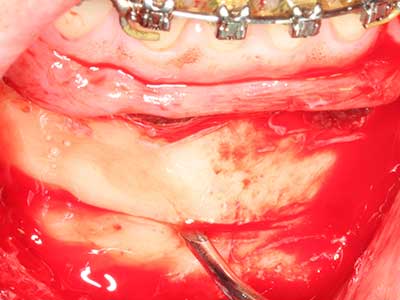

La preparación de la ventana lateral en la elevación del suelo del seno maxilar representa un enorme reto, sobre todo para profesionales de la implantalogía que tienen poca experiencia en técnicas quirúrgicas. Retirar la cobertura ósea del seno maxilar sin provocar daños en la membrana de Schneider es tan solo una parte de la operación; tras crear un acceso suficiente, es preciso movilizar con cuidado la mucosa del seno maxilar a fin de dejar espacio para el material o los implantes que vayan a incorporarse. En esta aplicación la cirugía piezoeléctrica resulta útil en dos sentidos: por un lado, el uso de insertos diamantados permite realizar una retirada selectiva del hueso y, si se actúa con cuidado, la membrana permanece intacta, y por otro lado, las frecuencias de ultrasonidos favorecen también un desprendimiento sin problemas de la membrana, pues se transfieren al espacio comprendido entre la mucosa y el suelo del seno maxilar gracias al uso de piezas romas especiales (Cassetta, Ricci et al. 2012, Pereira, Gealh et al. 2014) (Rickert, Vissink et al. 2013). De este modo, no es de extrañar los trabajos publicados en la actualidad sobre la técnica de elevación del suelo del seno maxilar mediante la técnica de Caldwell-Luc con instrumentos piezoeléctricos (Wallace, Tarnow et al. 2012).

En la extracción de bloques óseos la piezocirugía también presenta ventajas adicionales: Además de la alta precisión en la osteotomía que ya se ha descrito antes, se ha comprobado que el uso de los delgados insertos de sierra resulta especialmente cuidadosas con el hueso. Frente a esto, sobre todo cuando se usan las fresas de Lindemann, cabe esperar pérdidas en la extracción significativamente más altas debido al mayor grosor de la parte frontal del cabezal (Lakshmiganthan, Gokulanathan et al. 2012). La separación basal que se necesita en particular en los injertos de bloque extraídos de forma retromolar se ve facilitada mediante sierras perpendiculares especialmente previstas a tal fin, lo que permite considerar que la cirugía piezoeléctrica es un procedimiento preciso y seguro para la obtención de bloques de hueso en el área retromolar (Happe 2007) (fig. 1-12).